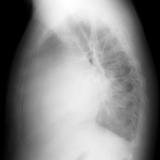

Case 3 Lat only

Peric calcification